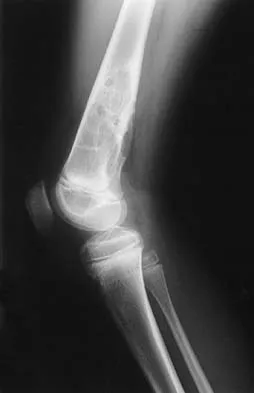

A 13-year-old girl is referred for a painful progressive valgus deformity of the right knee. Examination reveals an antalgic gait with an obvious valgus deformity. The right distal femur has a palpable, tender mass with erythema and warmth. Figures 4a and 4b show a clinical photograph and a radiograph. Management should consist of

Explanation

The radiograph shows a pathologic fracture through a destructive lesion of the distal femur metaphysis with osteolytic and osteoblastic features. The lateral cortex is destroyed, and there is periosteal new bone formation. These findings are consistent with malignancy, most likely an osteogenic sarcoma. Patients with suspected malignant tumors are best managed by surgeons with specific expertise in orthopaedic oncology. The biopsy of a malignant lesion should be deferred to the surgeon who is capable of definitive management of the patient. Enneking W: Principles of musculoskeletal oncologic surgery, in Evarts C (ed): Surgery of the Musculoskeletal System. New York, NY, Churchill Livingston, 1990.